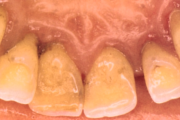

- igemepiir on taandunud (3)

- vahed hammaste vahel (5)

- hammaste tundlikkus (9)

- hammaste asukoha muutus (5)